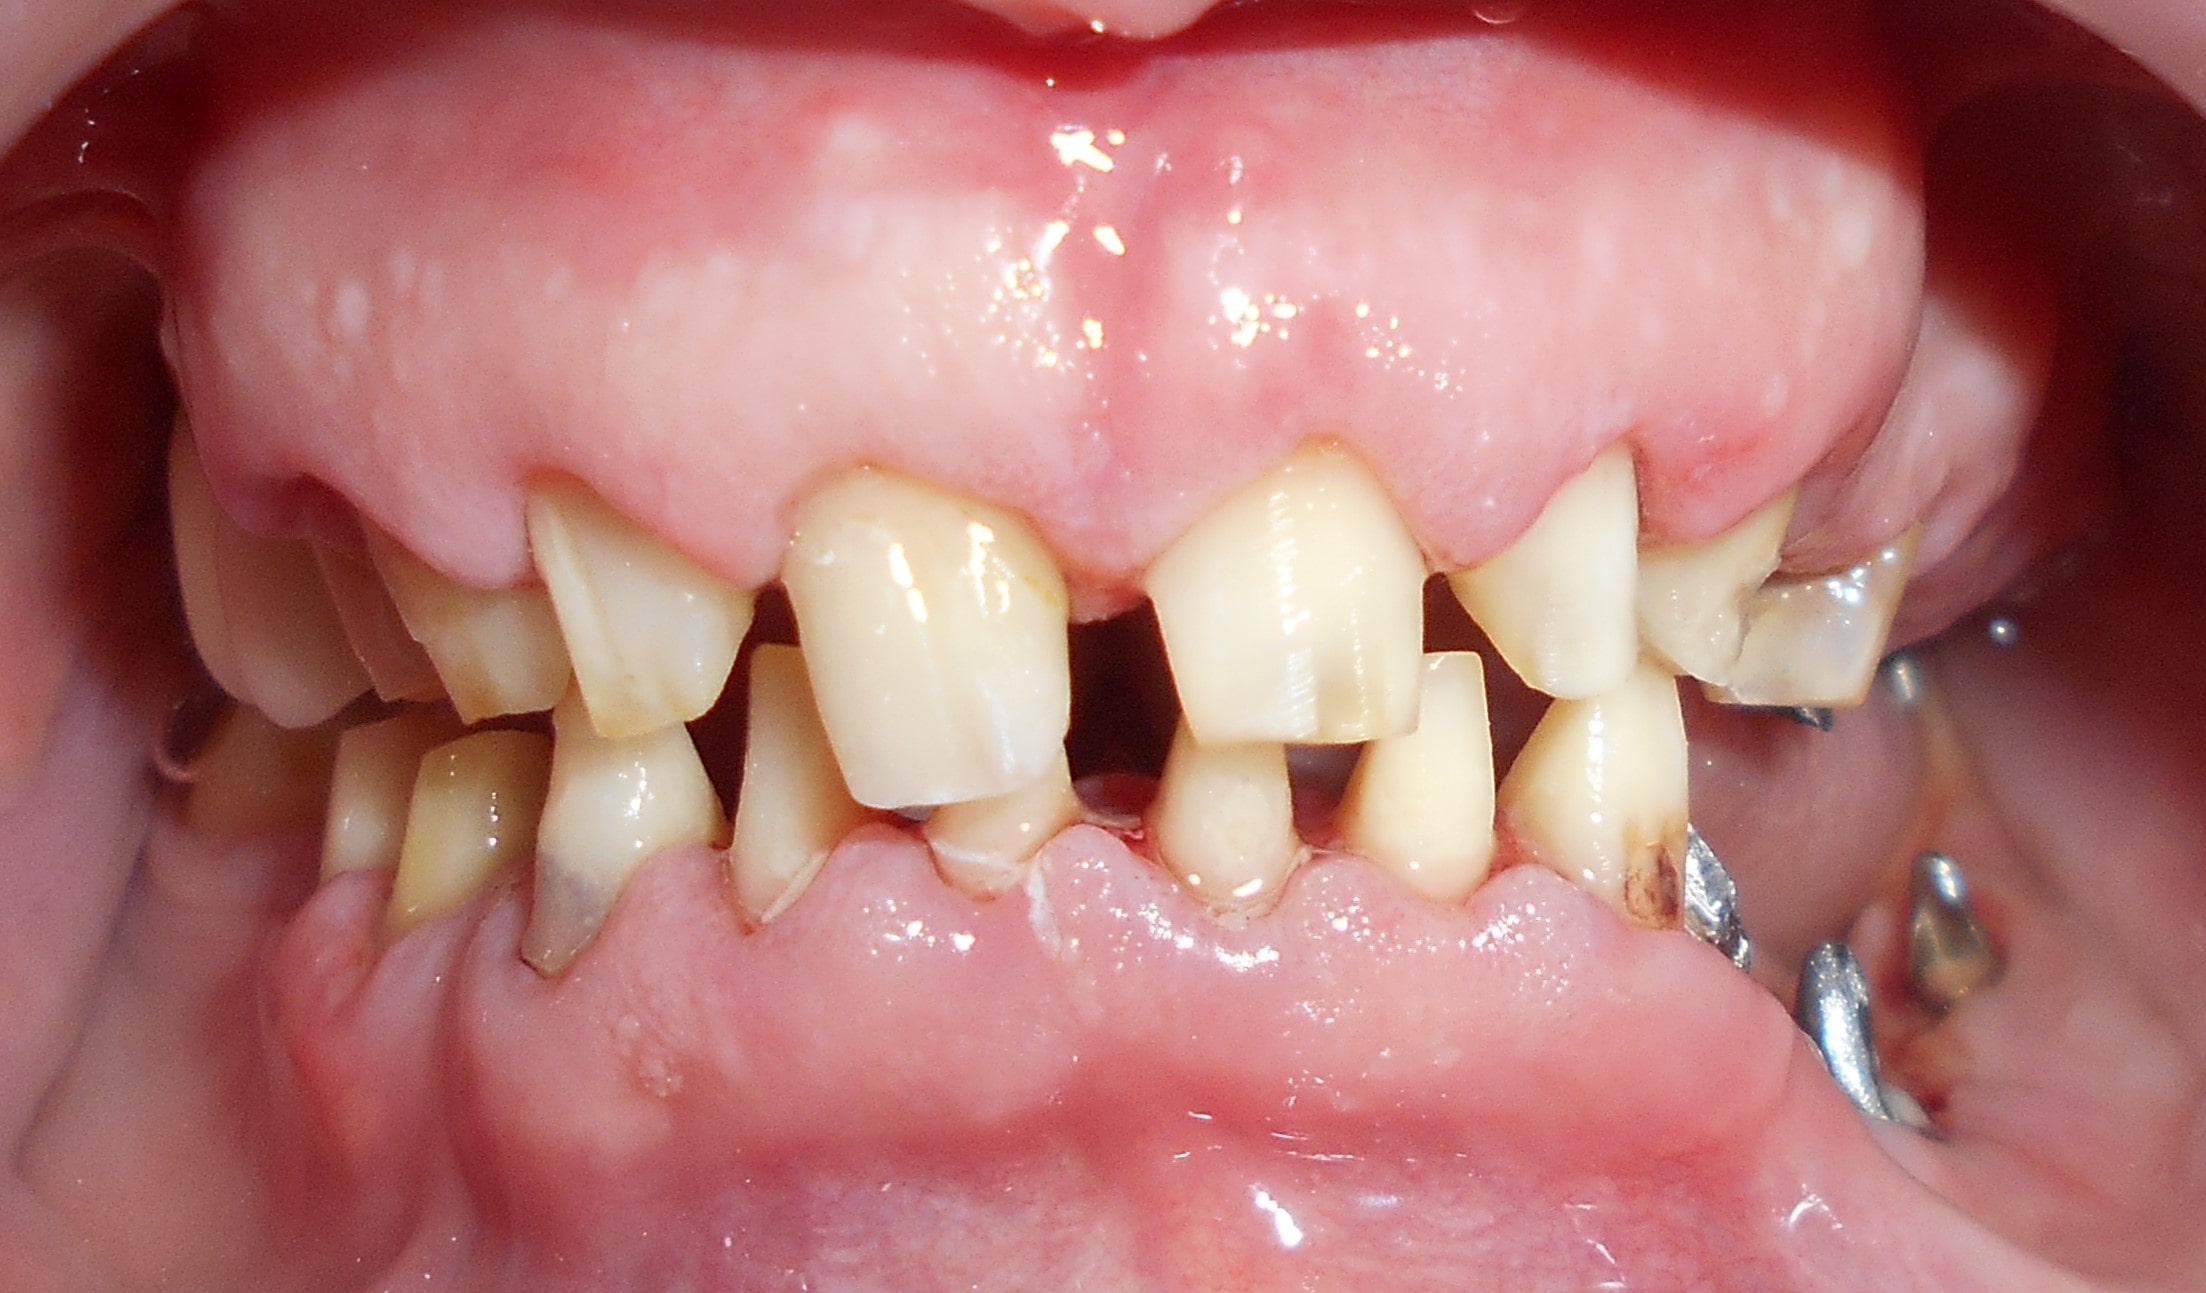

Pacijent 4

Pacijent iz inostranstva doalzi sa totalnom protezom u gornjoj vilici i sa uznapredovalom parodontopatijom preostalih zuba u donjoj vilici. Pacijent navodi da su mu u inostranstvu rekli da je nemoguće u gornjoj vilici ugraditi implantate bez velikih hirurških zahvata koji podrazumevaju transplantaciju kosti sa udaljenih delova tela i sinus lift proceduru. U gronjoj vilici je bila minimalna količina kosti sa izraženo spuštenim sinusima i sa minimalno vretikalnom i horizontalnom visinom kosti. Naše rešenje se sastojalo u sledećem: ugradnja deset implantata u gornjoj vilici u raspoloživu kost sa ugrdnjom veće količine veštačke kosti, od deset ugrađenih implanta dva implantata su tuberopterigoidna koji su zamenili sinus lift proceduru. U gornjoj vilici smo se opredelili za ugradnju većeg broja implantata kako bi prilikom izrade fiksnog protetskog rada dobili ravnomeran prenos pritiska žvakanja na implantate. U donjoj vilici intervencija je bila istovremena i ona je podrzumevala vađenje svih preostalih zuba i ugradnju osam implantata. Kompletno zbrinjavanje koje obuhvata hiruršku i protetsku fazu je trajalo tri meseca, tokom kojih je pacijent u gornjoj vilici bio zbrinut sa privremenom totalnom protezom, a u donjoj vilici sa fiksnim privremenim zubima koji su bili fiksirani na tek ugrađenim implantatima. Definitivni protetski rad je uspešno završen sa cirkonijum keramičkim - bezmetalnim mostovim pre četiri godine.